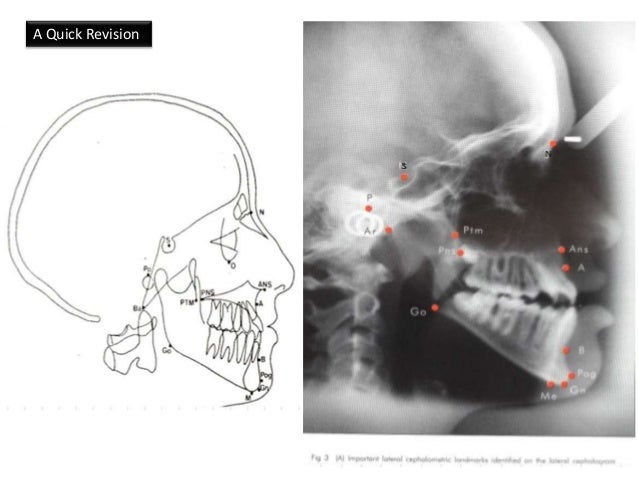

Cephalometric Tracing Landmarks